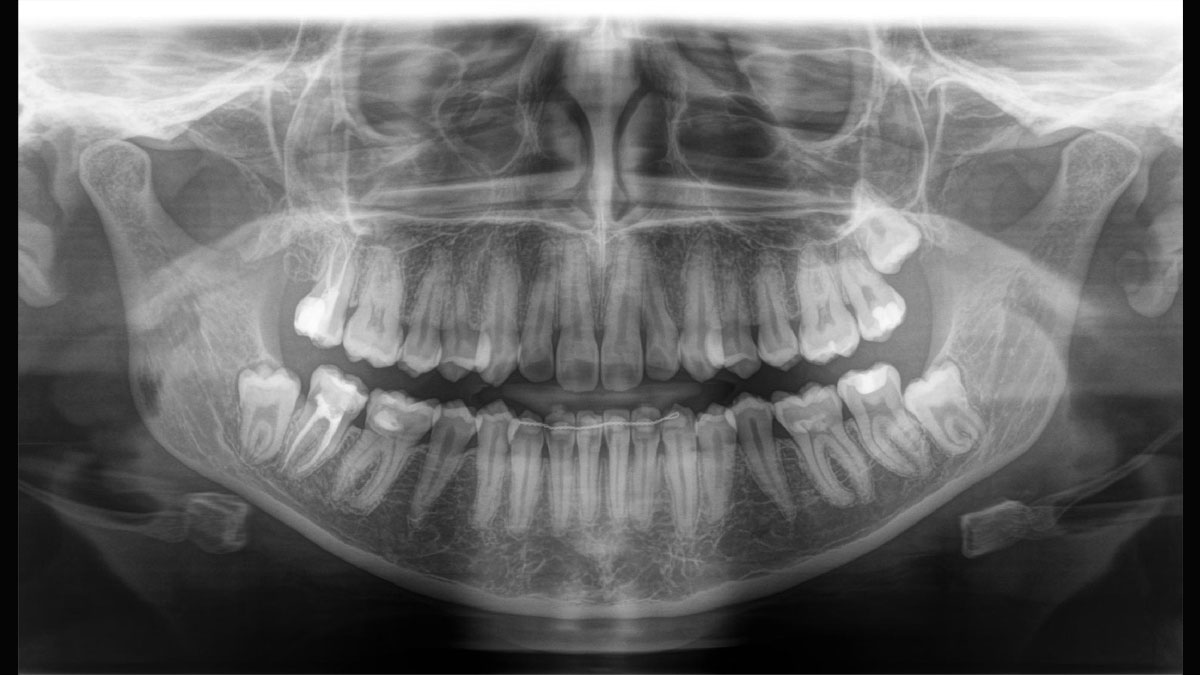

Der 2D/3D Power Performer Orthophos SL ist eine großartige Wahl für alle, die einfach mehr wollen. Der integrierte Direct Conversion Sensor (DCS) wurde für anspruchsvolle Bildqualitätsstandards entwickelt und bietet detaillierte Daten. Der intelligente Autofokus liefert automatisch fokussierte Panoramabilder mit hervorragender Gesamtschärfe. Orthophos SL bietet höchsten Bedienkomfort durch automatische Positionierung, eine anwenderfreundliche, intuitive Bedienung mit dem EasyPad und ein individuell einstellbares Umgebungslicht für ein exklusives Erscheinungsbild.

Der Autofokus erzeugt aus mehreren tausend Einzelbildern automatisch eine beeindruckende scharfe Panorama-Röntgenaufnahme

Es stehen mehrere Panoramaprogramme für Erwachsene und Kinder (Norm, Bissflügel, Nebenhöhlen usw.) zur Verfügung. Ein Ceph-Arm (links oder rechts) kann zum Zeitpunkt des Kaufs mitgeliefert oder später bei Bedarf nachgerüstet werden

Der Direct Conversion Sensor (DCS) hat den Standard der Panorama-Bildgebung neu definiert. Röntgenstrahlen werden direkt in elektrische Signale umgewandelt – im Gegensatz zu herkömmlichen Systemen gibt es keinen Signalverlust durch Lichtumwandlung, was eine verbesserte Bildgebung ermöglicht. Das Ergebnis sind Bilder mit einer sehr hohen Schärfe, selbst bei niedriger Dosis.

Eine Röntgenaufnahme muss sofort diagnostizierbar sein. Der Autofokus hilft dabei erheblich. Orthophos SL erfasst mehrere tausend Einzelbilder in einem Zyklus und erkennt automatisch scharfe Bereiche, um ein gleichmäßig scharfes Gesamtbild zu erzeugen. Der intelligente Autofokus erfordert keine manuellen Arbeitsschritte vor und nach der Erfassung.